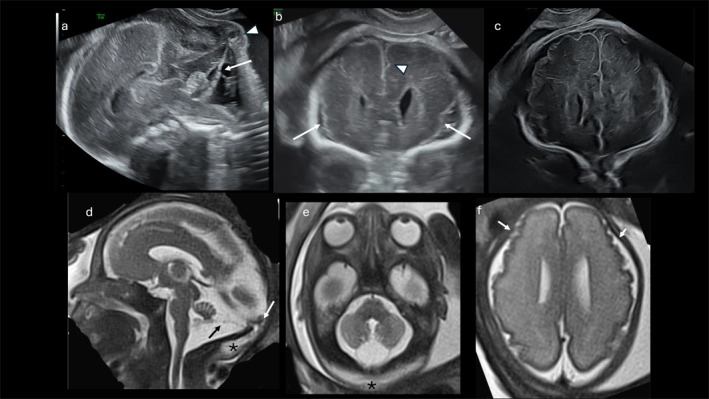

Knobloch Syndrome-1 is a rare autosomal recessive disorder typically diagnosed postnatally and characterized by occipital encephalocele, high myopia, and vitreoretinal degeneration. We describe a fetus with a constellation of prenatal neuroimaging findings, including occipital cephalocele, vermian dysplasia, bilateral polymicrogyria, and ocular elongation, that prompted genetic investigation. Trio exome sequencing identified biallelic pathogenic variants in COL18A1, confirming the diagnosis of Knobloch Syndrome-1. This case highlights how advanced fetal neuroimaging and prenatal exome sequencing can facilitate early recognition of syndromes like Knobloch, and underscores the importance of considering COL18A1-related disorders when multiple central nervous system anomalies are detected prenatally.